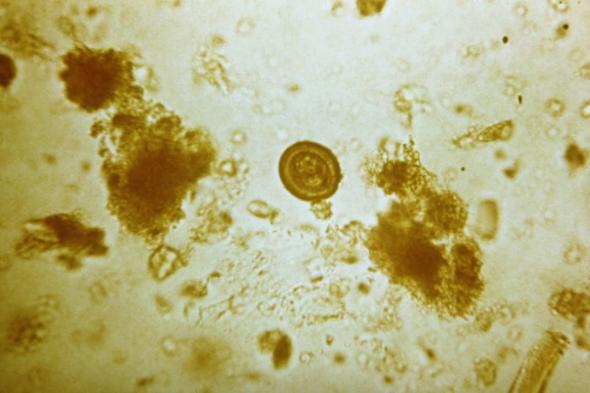

T soliumGetty Images

Las impactantes imágenes mostraban una enfermedad parasitaria llamada cisticercosis. Dicha dolencia es causada por la ingestión de huevos de la T solium. Estos se encuentran en los alimentos contaminados. La autoinfección se presenta cuando una persona ya infectada con T solium adulto ingiere luego los huevos. Esto ocurre por no lavarse bien las manos después de una deposición (transmisión fecal-oral).